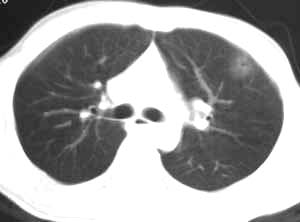

所以我认为应该首先考虑创伤性湿肺,只是需要楼主详细询问病史,排除炎性感染的可能。

病灶在纵隔窗没有显示,考虑是渗出性病变,结合外伤史我认为应该首先考虑创伤性湿肺

创伤性湿肺短期内有明显的变化,请把复查的图片继续上传.

一句话,有明确的外伤史,就要诊断肺挫伤.短期随访起到鉴别诊断作用.

考虑创伤性湿肺,建议治疗后复查。